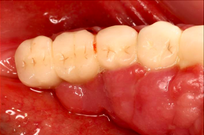

Before Treatment

A 65-year-old female on antihypertensives and immunosuppressants presented with severe gum swelling, inability to chew, and difficulty maintaining oral hygiene. This led to multiple decayed and periodontally compromised teeth, worsening her overall condition.

Drug-influenced gingival overgrowth or ‘DIGO’ in short, manifests as abnormal swelling of the gingiva.

- The condition is usually caused by adverse reactions to certain drugs such as antihypertensives, anticonvulsants or immunosuppressants.

- As the gum tissues become significantly larger, it may impede normal masticatory function, daily oral hygiene, and aesthetics, severely diminishing one’s quality of life. (Sabarudin et al. 2022)